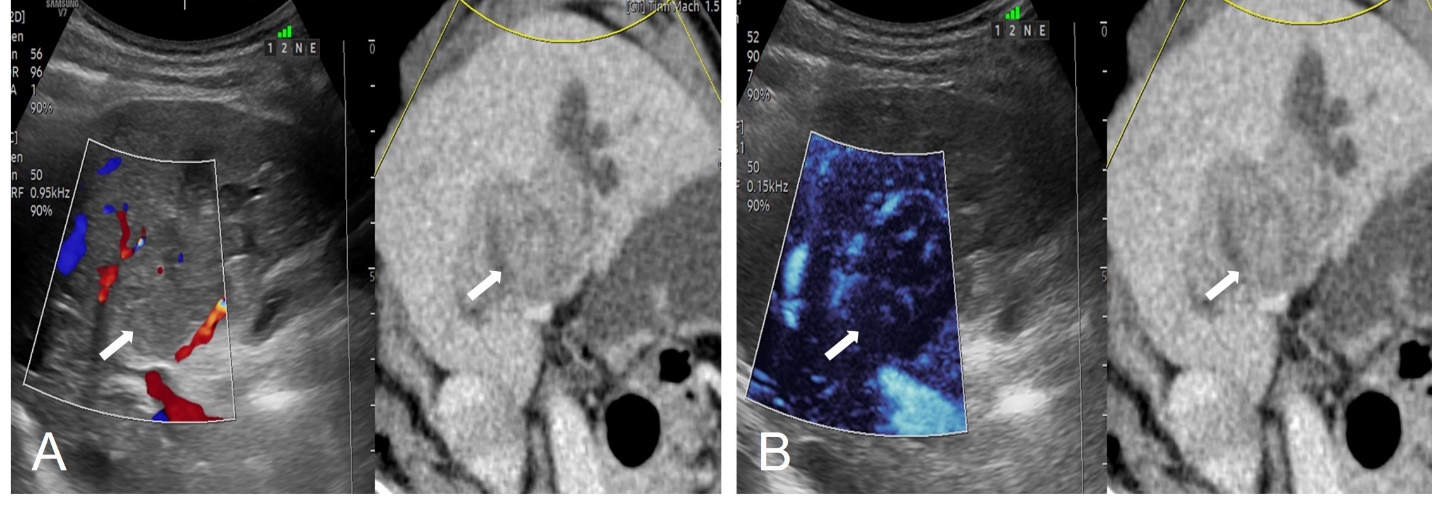

Hình 2: Hình ảnh hòa hình siêu âm với CLVT thì tĩnh mạch, kết hợp Doppler màu (A) và vi mạch trên cùng màn hình siêu âm (B). Trên siêu âm thường quy, tổn thương đồng âm với nhu mô gan cùng với việc có khí toàn bộ đường mật trong gan nên rất khó phát hiện. Chúng tôi sử dụng kỹ thuật hoà hình để xác định chính xác vị trí tổn thương cần sinh thiết lấy mẫu bệnh phẩm trên siêu âm, đối chiếu tương ứng với tổn thương trên CLVT (mũi tên).